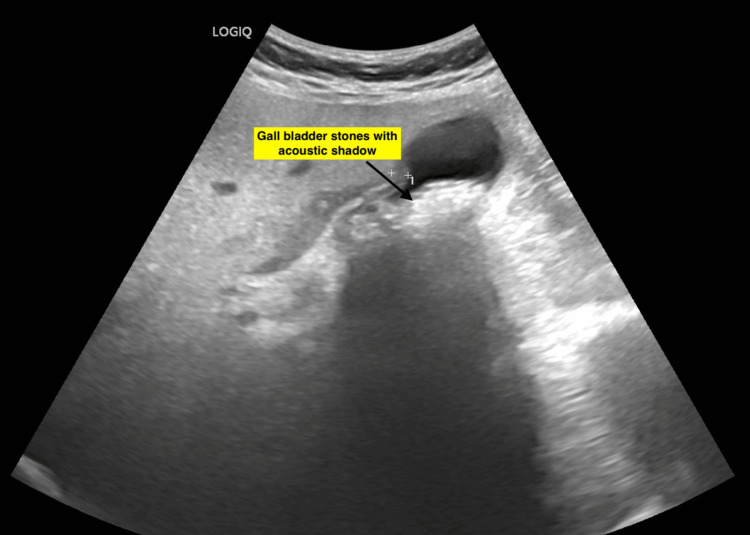

A 62-year-old woman presented with a four-day history of fever, right upper quadrant colicky abdominal pain, and nausea. Prior medical history included diabetes mellitus and hypertension, both well-controlled with medications. Two prior episodes of biliary colic had been managed conservatively. On physical examination, right hypochondriac tenderness was noted. Icterus was absent. Ultrasound imaging revealed multiple stones within the gallbladder (Figure 1).